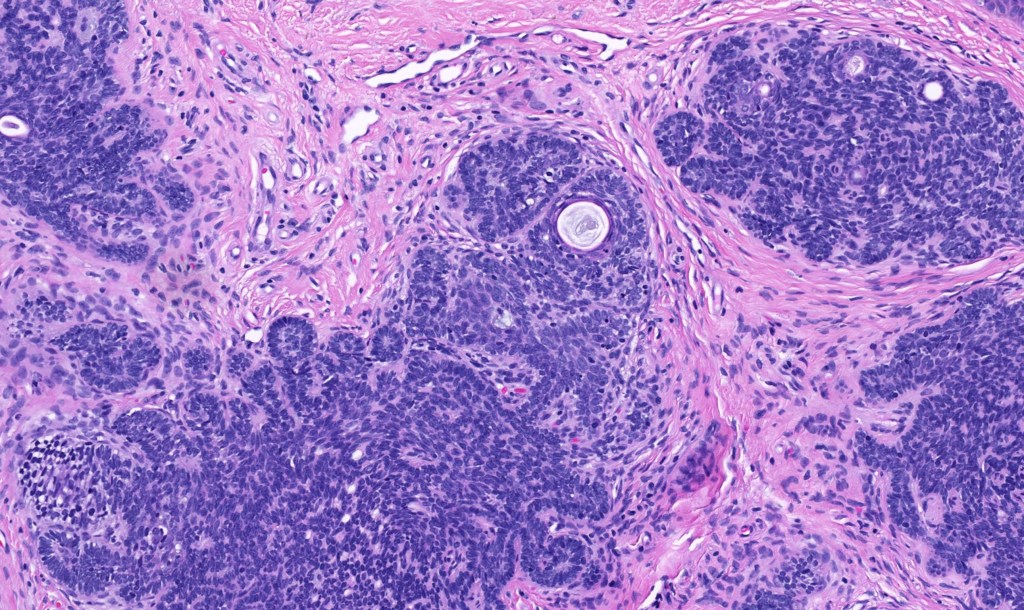

•The classical appearance consists of keratocysts & lobules of basaloid cells

•Basaloid lobules show peripheral palisading

•Perifollicular mesenchyme is always conspicuous and sometimes densely aggregated are seen indenting the baslaloid lobules (papillary mesenchymal bodies)

Trichoepithelioma should be distinguished from trichoblastoma since the latter is very rarely syndromic. Trichoepithelioma is largely a dermal tumor whereas trichoblastoma often extends from the dermis into subcutaneous fat or deeper in very large examples. Papillary mesenchymal bodies are much better formed and generally more obvious in trichoepithelioma. Trichoepithelioma must also be distinguished from basal cell carcinoma. Retraction artifact & stromal mucin are features of basal cell carcinoma and not trichoepithelioma. Papillary mesenchymal bodies are not seen in basal cell carcinoma.